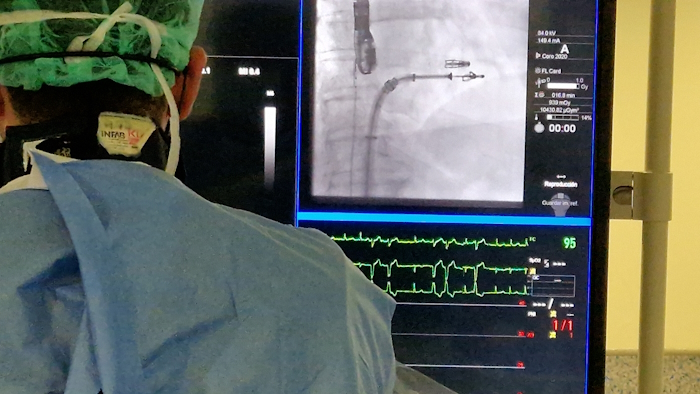

Oviedo, 15 de octubre de 2025 – El servicio de cardiología del Hospital Universitario Central de Asturias (HUCA) ha realizado con éxito el primer procedimiento en España guiado con la sonda VeriSight Pro 3D de Philips, una innovación pionera en ecocardiografía intracardíaca (ICE). “El nuevo catéter nos ha permitido tratar la válvula tricúspide de una forma mucho más precisa”, ha explicado el doctor Pablo Avanzas, director del Área de Gestión Clínica del Corazón del HUCA, en una rueda de prensa realizada en el hospital asturiano.

El 14 de octubre se trataron en el HUCA tres pacientes portadores de una misma patología, la insuficiencia tricúspide grave. Se realizaron las tres intervenciones, implantando varios dispositivos Triclip, guiado con la nueva tecnología, de forma exitosa y sin complicaciones. En comparación con la ecografía transesofágica (ecografía utilizada de forma estándar en el momento actual), la nueva sonda mostró unas imágenes de mejor calidad, lo que facilitó el tratamiento de las mismas mediante la terapia de aproximación borde a borde.

El catéter VeriSight Pro ofrece imágenes 3D en tiempo real directamente dentro del corazón, ayudando a los médicos a realizar procedimientos con mayor eficacia y seguridad: “Esto se traduce en una mayor precisión a la hora de guiar los procedimientos estructurales, como el cierre de comunicaciones interauriculares, la reparación de válvulas o la implantación de dispositivos intracardiacos, mejorando la seguridad y la eficacia de las intervenciones”, según el director del Área del Corazón.

El doctor Avanzas y su equipo han podido evaluar la anatomía, guiar la colocación de dispositivos y confirmar los resultados del procedimiento, todo ello desde un único punto de acceso.